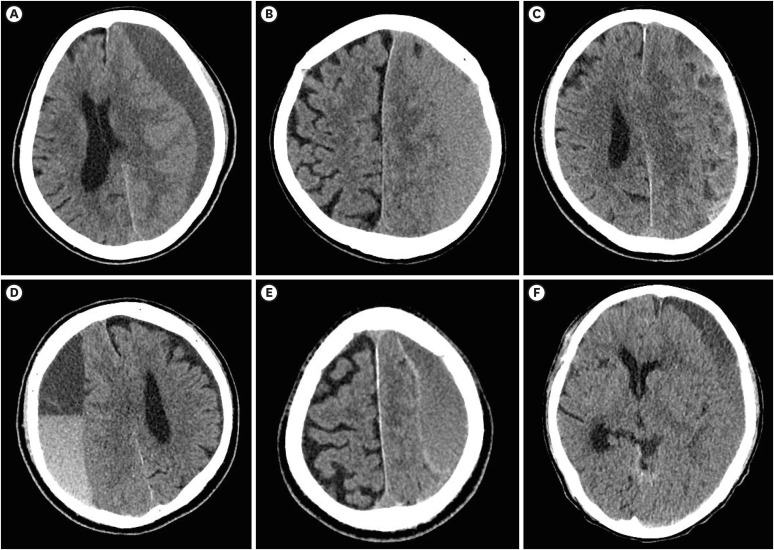

Results: Of the 370 patients, 345 (93.2%) had no recurrence and 25 (6.8%) had recurrence. Univariate and multivariate analyses revealed that male sex, advanced age, bilateral hematoma, moderate or severe brain atrophy, separation type, gradation type, and burr hole trephination were independent risk factors for CSDH recurrence.

Conclusion: Sex, age, bilateral hematoma, brain atrophy, hematoma density and architecture, and surgical techniques are all associated with CSDH recurrence.